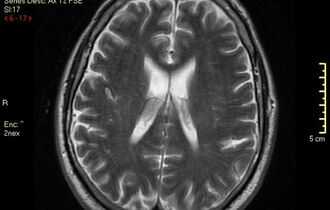

Особенности отображения туберкулеза на МРТ-снимке

Рентгенолог делает выводы о том, что у человека туберкулез на основании просмотра снимков, а также изучения проработанной трехмерной модели, которая была создана томографом.

Основной признак туберкулеза на снимке - заметные уплотнения ткани легкого. Они могут быть как единичными, так и множественными. Основная область расположения - рядом с бронхами.

Также о заболевании говорит заметное увеличение лимфатических узлов. Конечный диагноз может поставить только врач.

Как выглядит туберкулез на снимке МРТ?

Туберкулез на КТ, как и на МРТ, диагностируют по основным признакам заболевания. Чаще других во время процедуры визуализируют на снимках:

- уплотнение легочной ткани - один или несколько очагов поражения рядом с бронхами;

- увеличенные лимфоузлы у корня легкого и средостения.

Только врач может распознать патологические очаги и вынести советующий диагноз.